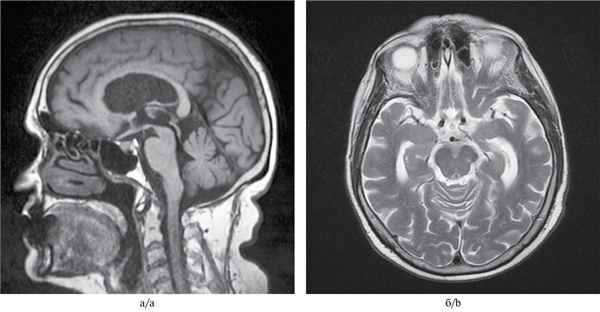

МРТ-исследование проведено на магнитно-резонансном томографе «Siemens» с напряженностью магнитного поля 1,5 Тл, с получением стандартных Т1- и Т2-взвешенных изображений (Т1-ВИ, Т2-ВИ) в фронтальной, аксиальной и сагиттальной плоскостях, с последующей оценкой визуальных изменений головного мозга (см. рисунок). Выявлены признаки атрофии среднего мозга с симптомами колибри в сагиттальной (см. рисунок, а) и Микки Мауса в аксиальной плоскостях (см. рисунок, б).

МРТ головного мозга 79-летней пациентки с ПНП.

а — Т1-взвешенное изображение, сагиттальная плоскость. Атрофия среднего мозга, сохранение объема моста и атрофия крыши среднего мозга. Симптом клюва колибри; б — Т2-взвешенное изображение на аксиальном срезе на уровне среднего мозга. Атрофия среднего мозга с формированием симптома Микки Мауса.

Учитывая прогрессирование заболевания в течение года, с постуральными нарушениями, акинетико-ригидным синдромом, параличом взора, дизартрией, умеренным когнитивным нарушением, стереотипными поведенческими нарушениями, данные МРТ головного мозга (атрофия среднего мозга), а также недавно возникший оромандибулярный гиперкинез на фоне приема противопаркинсонического препарата, выставлен диагноз «ПНП с леводопа-индуцированной дискинезией в виде оромандибулярного гиперкинеза».